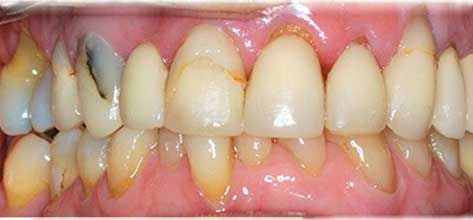

En la primera fotografía se observan coronas envejecidas, diferencias de color y desgaste generalizado. En el después se aprecia una restauración mucho más armónica, con coronas renovadas que mejoran la estética, la uniformidad y la función de la sonrisa.